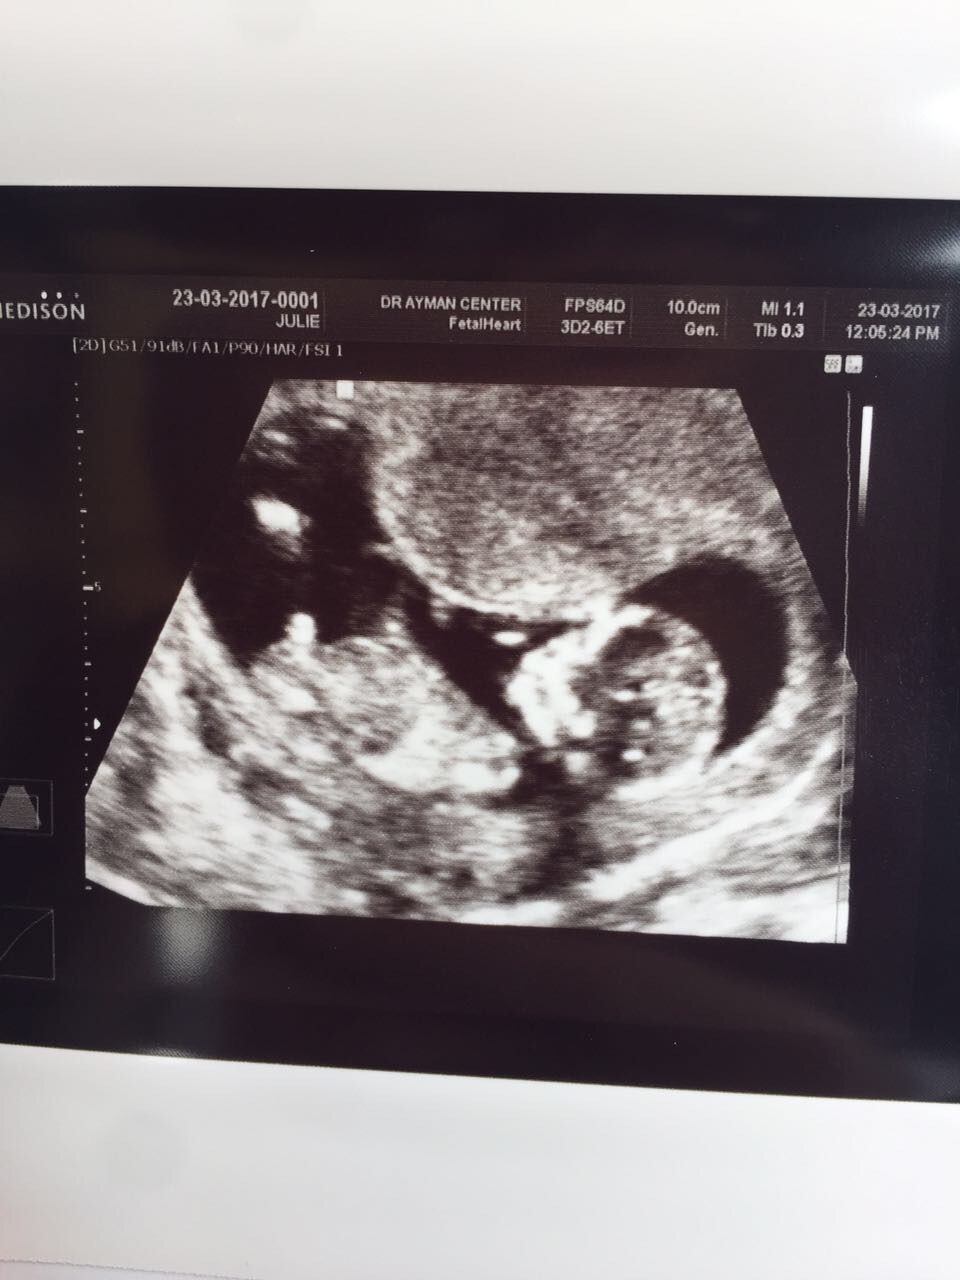

I had my nt scan at 12 weeks. dr say its 85% boy I wanted to get some opinions. Thanks!Attachment 35604